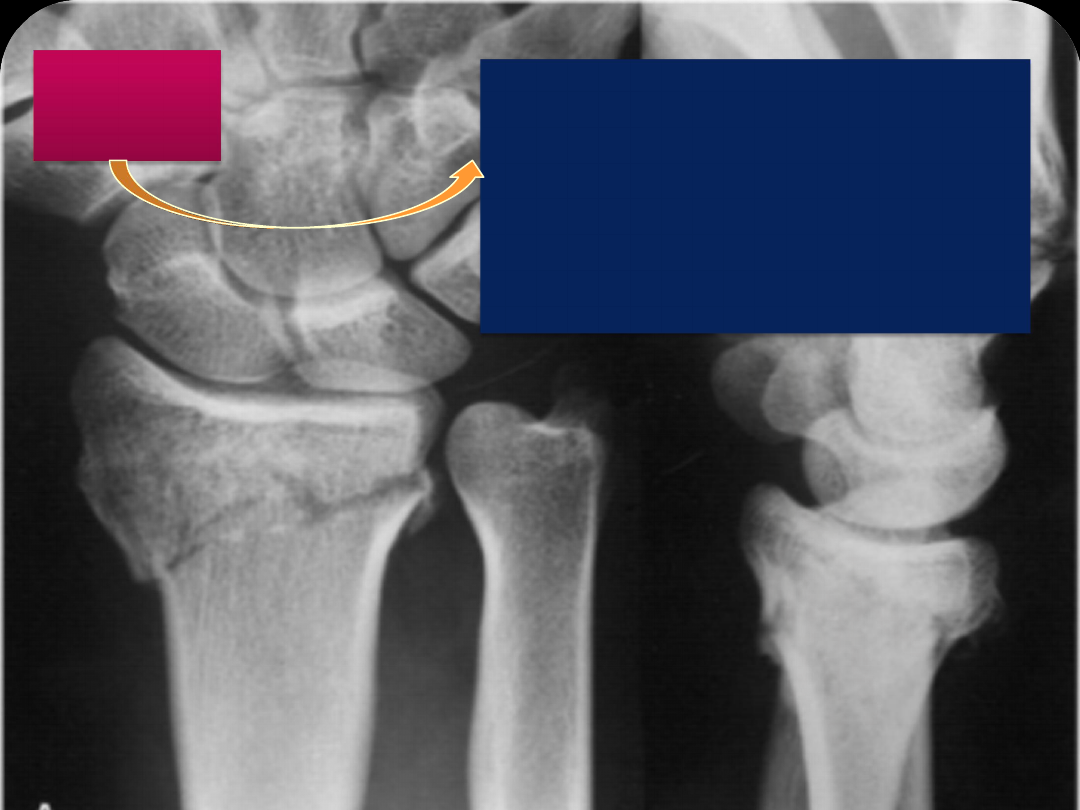

The   anteroposterior  radiograph  on  the  left illustrates normal radial

inclination of  approximately 22  degrees.  The lateral radiograph  on

the  right illustrates normal volar tilt of  the distal articular surface  of

approximately 11 degrees.